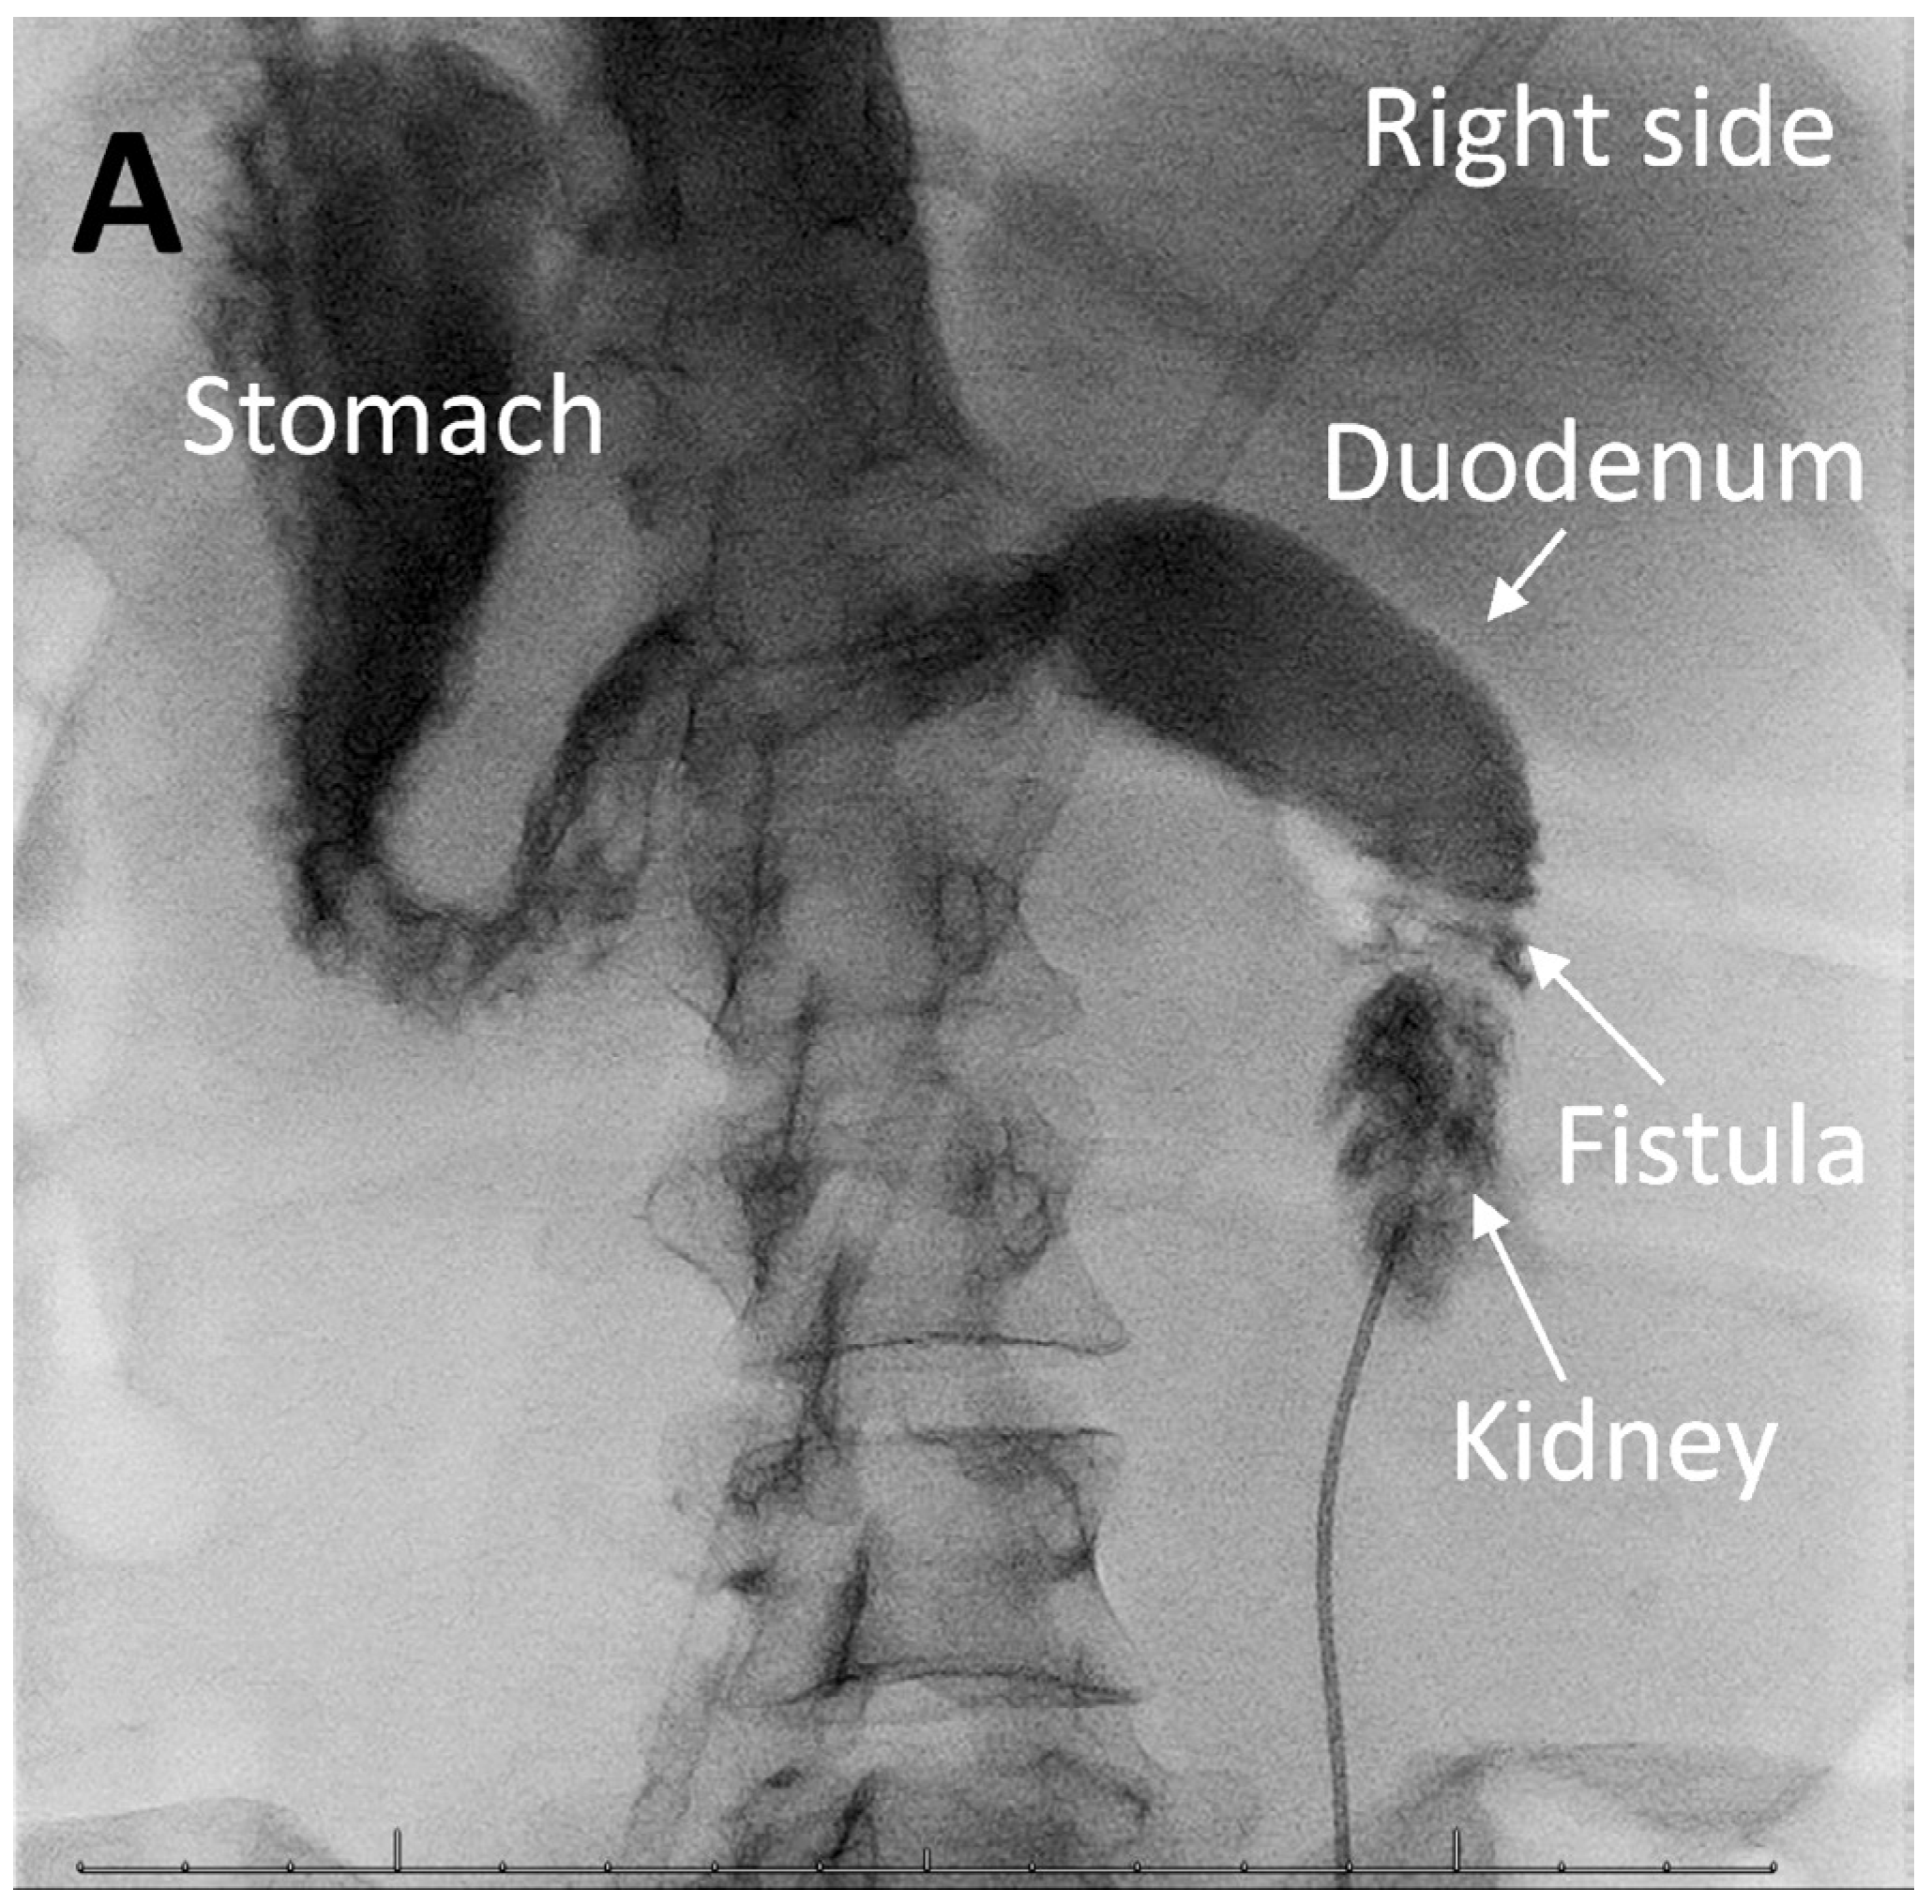

Pyeloduodenal Fistula in Xanthogranulomatous Pyelonephritis